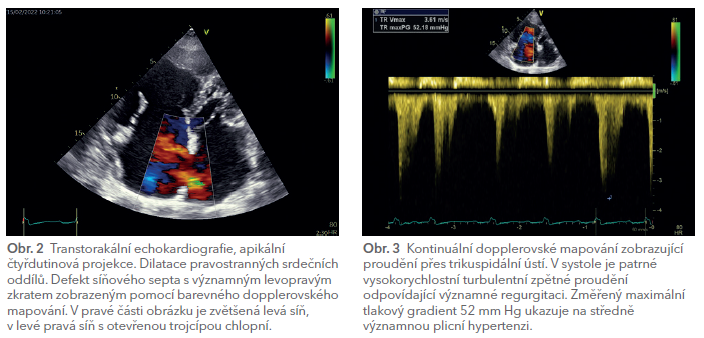

Rozhodující význam pro stanovení diagnózy mělo echokardiografické vyšetření (obr. 2). Již při transtorakálním echokardiografickém vyšetření (TTE) byla patrná především významná dilatace pravostranných srdečních oddílů i levé síně a výpadek odrazů ve střední části síňového septa, který odpovídal velkému defektu. Barevné dopplerovské mapování pak zobrazilo široké zkratové proudění z levé do pravé síně. Na trikuspidální chlopni (obr. 3) byla zachycena středně významná regurgitace podmíněná dilatací prstence chlopně a přítomnou plicní arteriální hypertenzí s echokardiograficky odhadovaným systolickým tlakem v plicnici 60 mm Hg. Levá komora byla nezvětšená, bez hypertrofie se symetrickou kontrakcí, s lehce sníženou systolickou funkcí (ejekční frakce 50 %). Byl popsán i malý perikardiální výpotek.

Následně bylo doplněno i transezofageální echokardiografické vyšetření (TEE), které po trojrozměrné rekonstrukci obrazu velmi názorně ukázalo velikost a tvar defektu síňového septa (obr. 4) s rozměry dosahujícími až 36,5 × 28 mm.